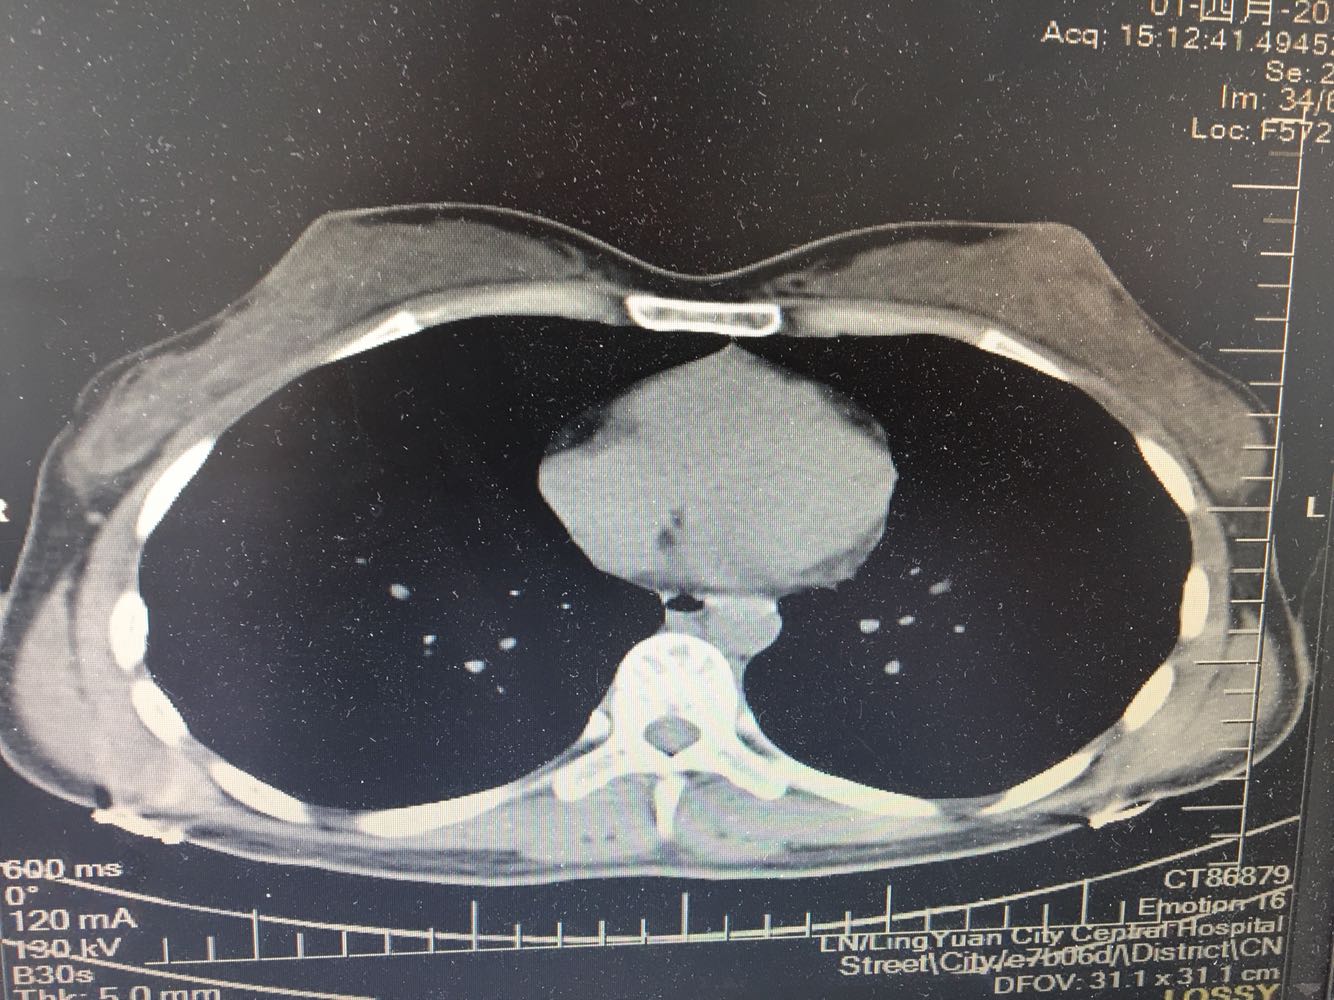

女,26岁,咳嗽1周,咳痰不畅,咽喉痒,口服阿莫西林无好转,昨日发热,体温38.5摄氏度,于门诊查肺CT后以肺炎收入院,病来无盗汗,无咳血,无消瘦及乏力,无头痛,无肢体酸痛,饮食睡眠可,二便正常

支原体肺炎?肺结核?

支原体抗体1:160,结核抗体弱阳性。支原体肺炎个别可见上叶病变,该患无结核中毒症状,考虑支原体肺炎可能性大,但肺尖为结核好发部位,需要抗炎治疗后复查观察疗效。